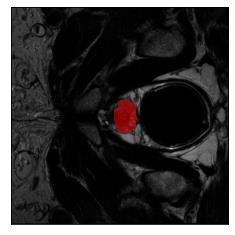

Machine learning models are typically deployed in a test setting that differs from the training setting, potentially leading to decreased model performance because of domain shift. If we could estimate the performance that a pre-trained model would achieve on data from a specific deployment setting, for example a certain clinic, we could judge whether the model could safely be deployed or if its performance degrades unacceptably on the specific data. Existing approaches estimate this based on the confidence of predictions made on unlabeled test data from the deployment's domain. We find existing methods struggle with data that present class imbalance, because the methods used to calibrate confidence do not account for bias induced by class imbalance, consequently failing to estimate class-wise accuracy. Here, we introduce class-wise calibration within the framework of performance estimation for imbalanced datasets. Specifically, we derive class-specific modifications of state-of-the-art confidence-based model evaluation methods including temperature scaling (TS), difference of confidences (DoC), and average thresholded confidence (ATC). We also extend the methods to estimate Dice similarity coefficient (DSC) in image segmentation. We conduct experiments on four tasks and find the proposed modifications consistently improve the estimation accuracy for imbalanced datasets. Our methods improve accuracy estimation by 18\% in classification under natural domain shifts, and double the estimation accuracy on segmentation tasks, when compared with prior methods.